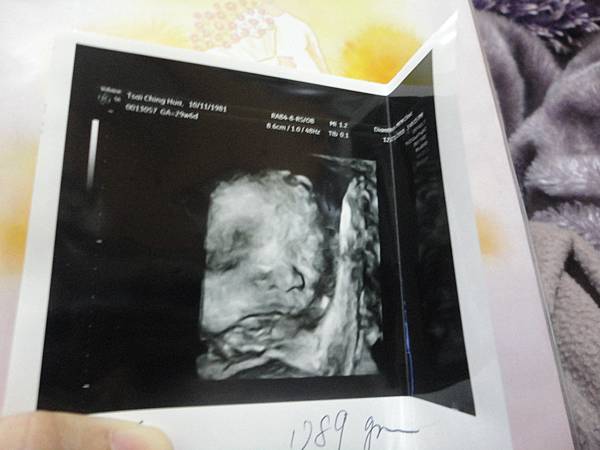

醫生一邊又給我看了所謂的3D

我第一次看到比較清楚的樂樂模樣

覺得還蠻新鮮的呢

(看起來好奇怪喔XDDDDDDD)